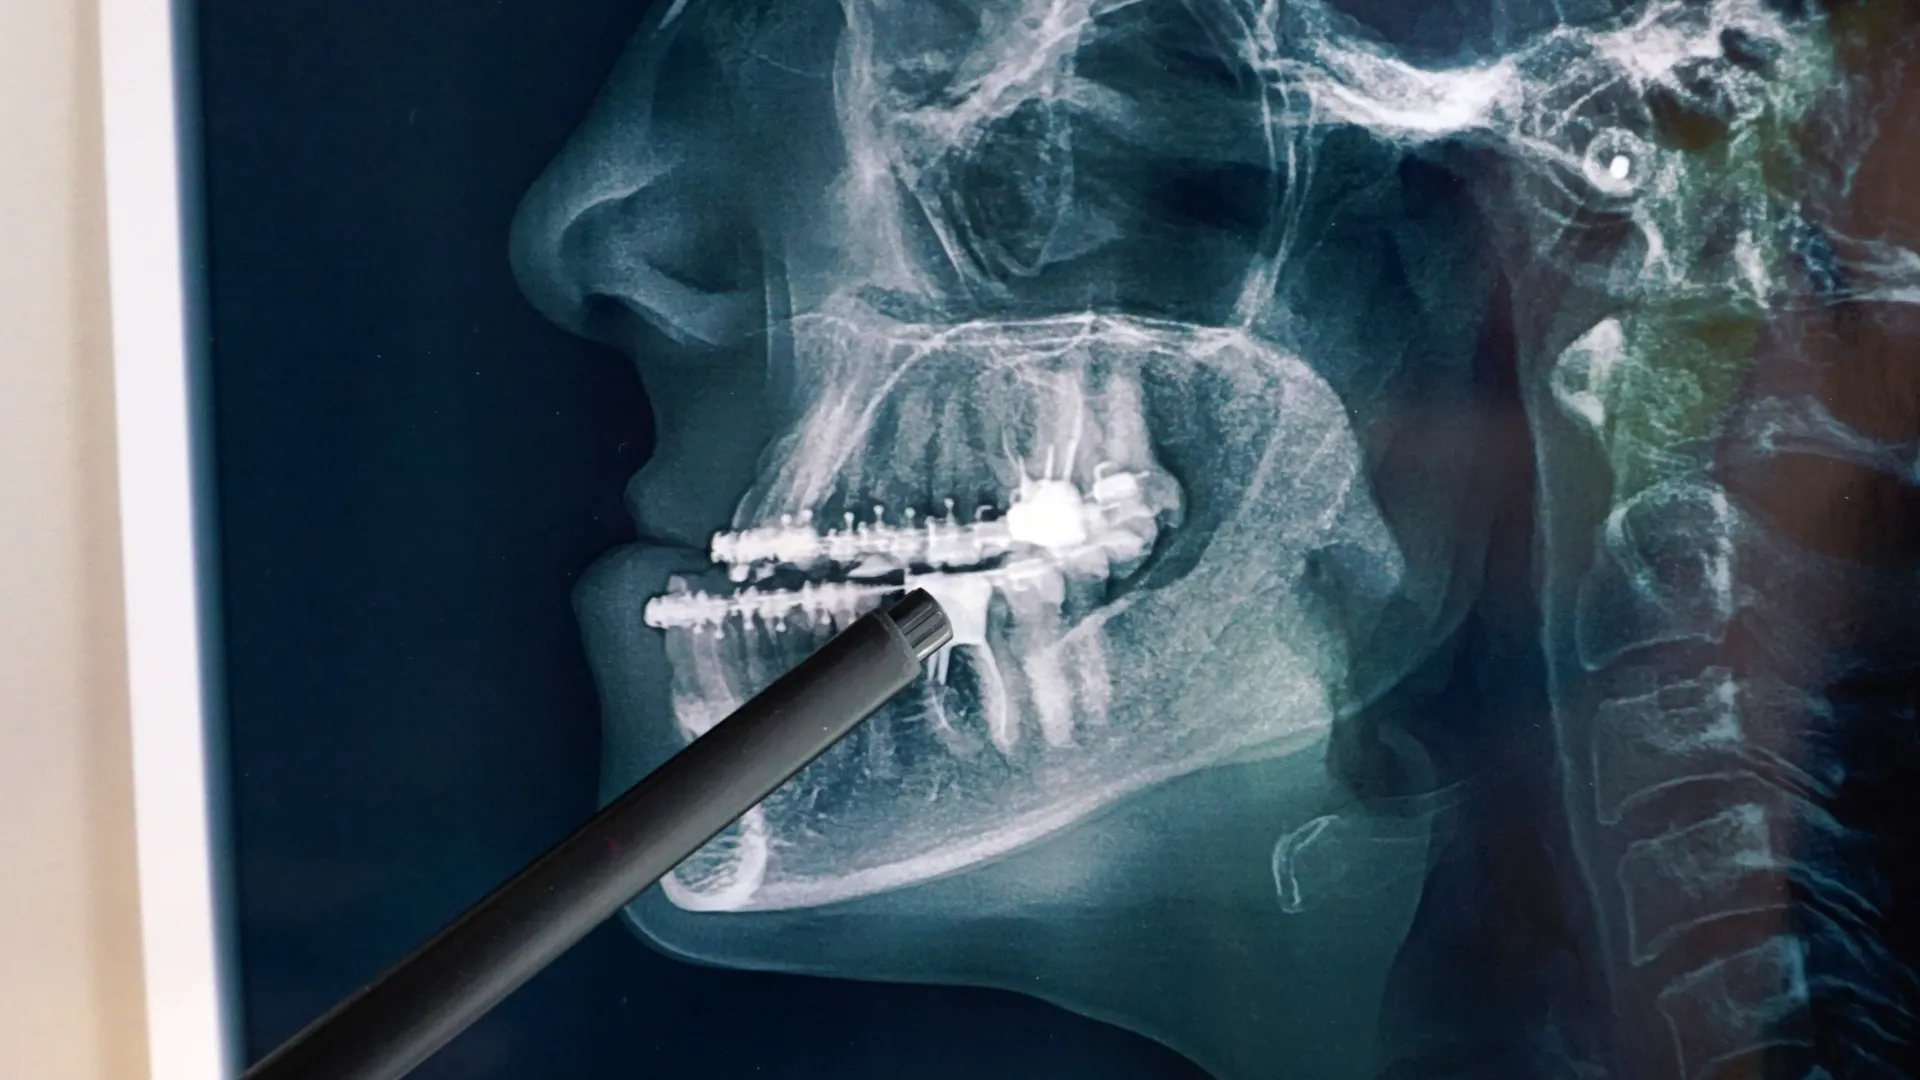

radiografía dental

Cirugía Maxilofacial

Es la especialidad médico-quirúrgica que se ocupa del estudio, diagnóstico, tratamiento y rehabilitación de las enfermedades, lesiones y malformaciones que afectan la cavidad bucal, la cara, los maxilares, el cuello y las estructuras cervicales relacionadas. Su campo de acción abarca tanto aspectos funcionales como estéticos.

Esta disciplina trata una amplia variedad de patologías, desde extracciones dentales complejas y colocación de implantes, hasta cirugías reconstructivas por traumatismos faciales, extirpación de tumores, corrección de malformaciones congénitas como el labio leporino o el paladar hendido, y tratamiento de trastornos de la articulación temporomandibular. También incluye procedimientos como la cirugía ortognática, que busca corregir la posición de los maxilares para mejorar la mordida y la armonía facial.

Las intervenciones pueden implicar el uso de placas, tornillos, injertos óseos o materiales biocompatibles para reconstruir estructuras dañadas o corregir deformidades. En muchos casos, el trabajo del cirujano maxilofacial se realiza en colaboración con otros profesionales como ortodoncistas, otorrinolaringólogos, oncólogos, anestesistas o logopedas, en un enfoque multidisciplinar que garantiza una atención integral.